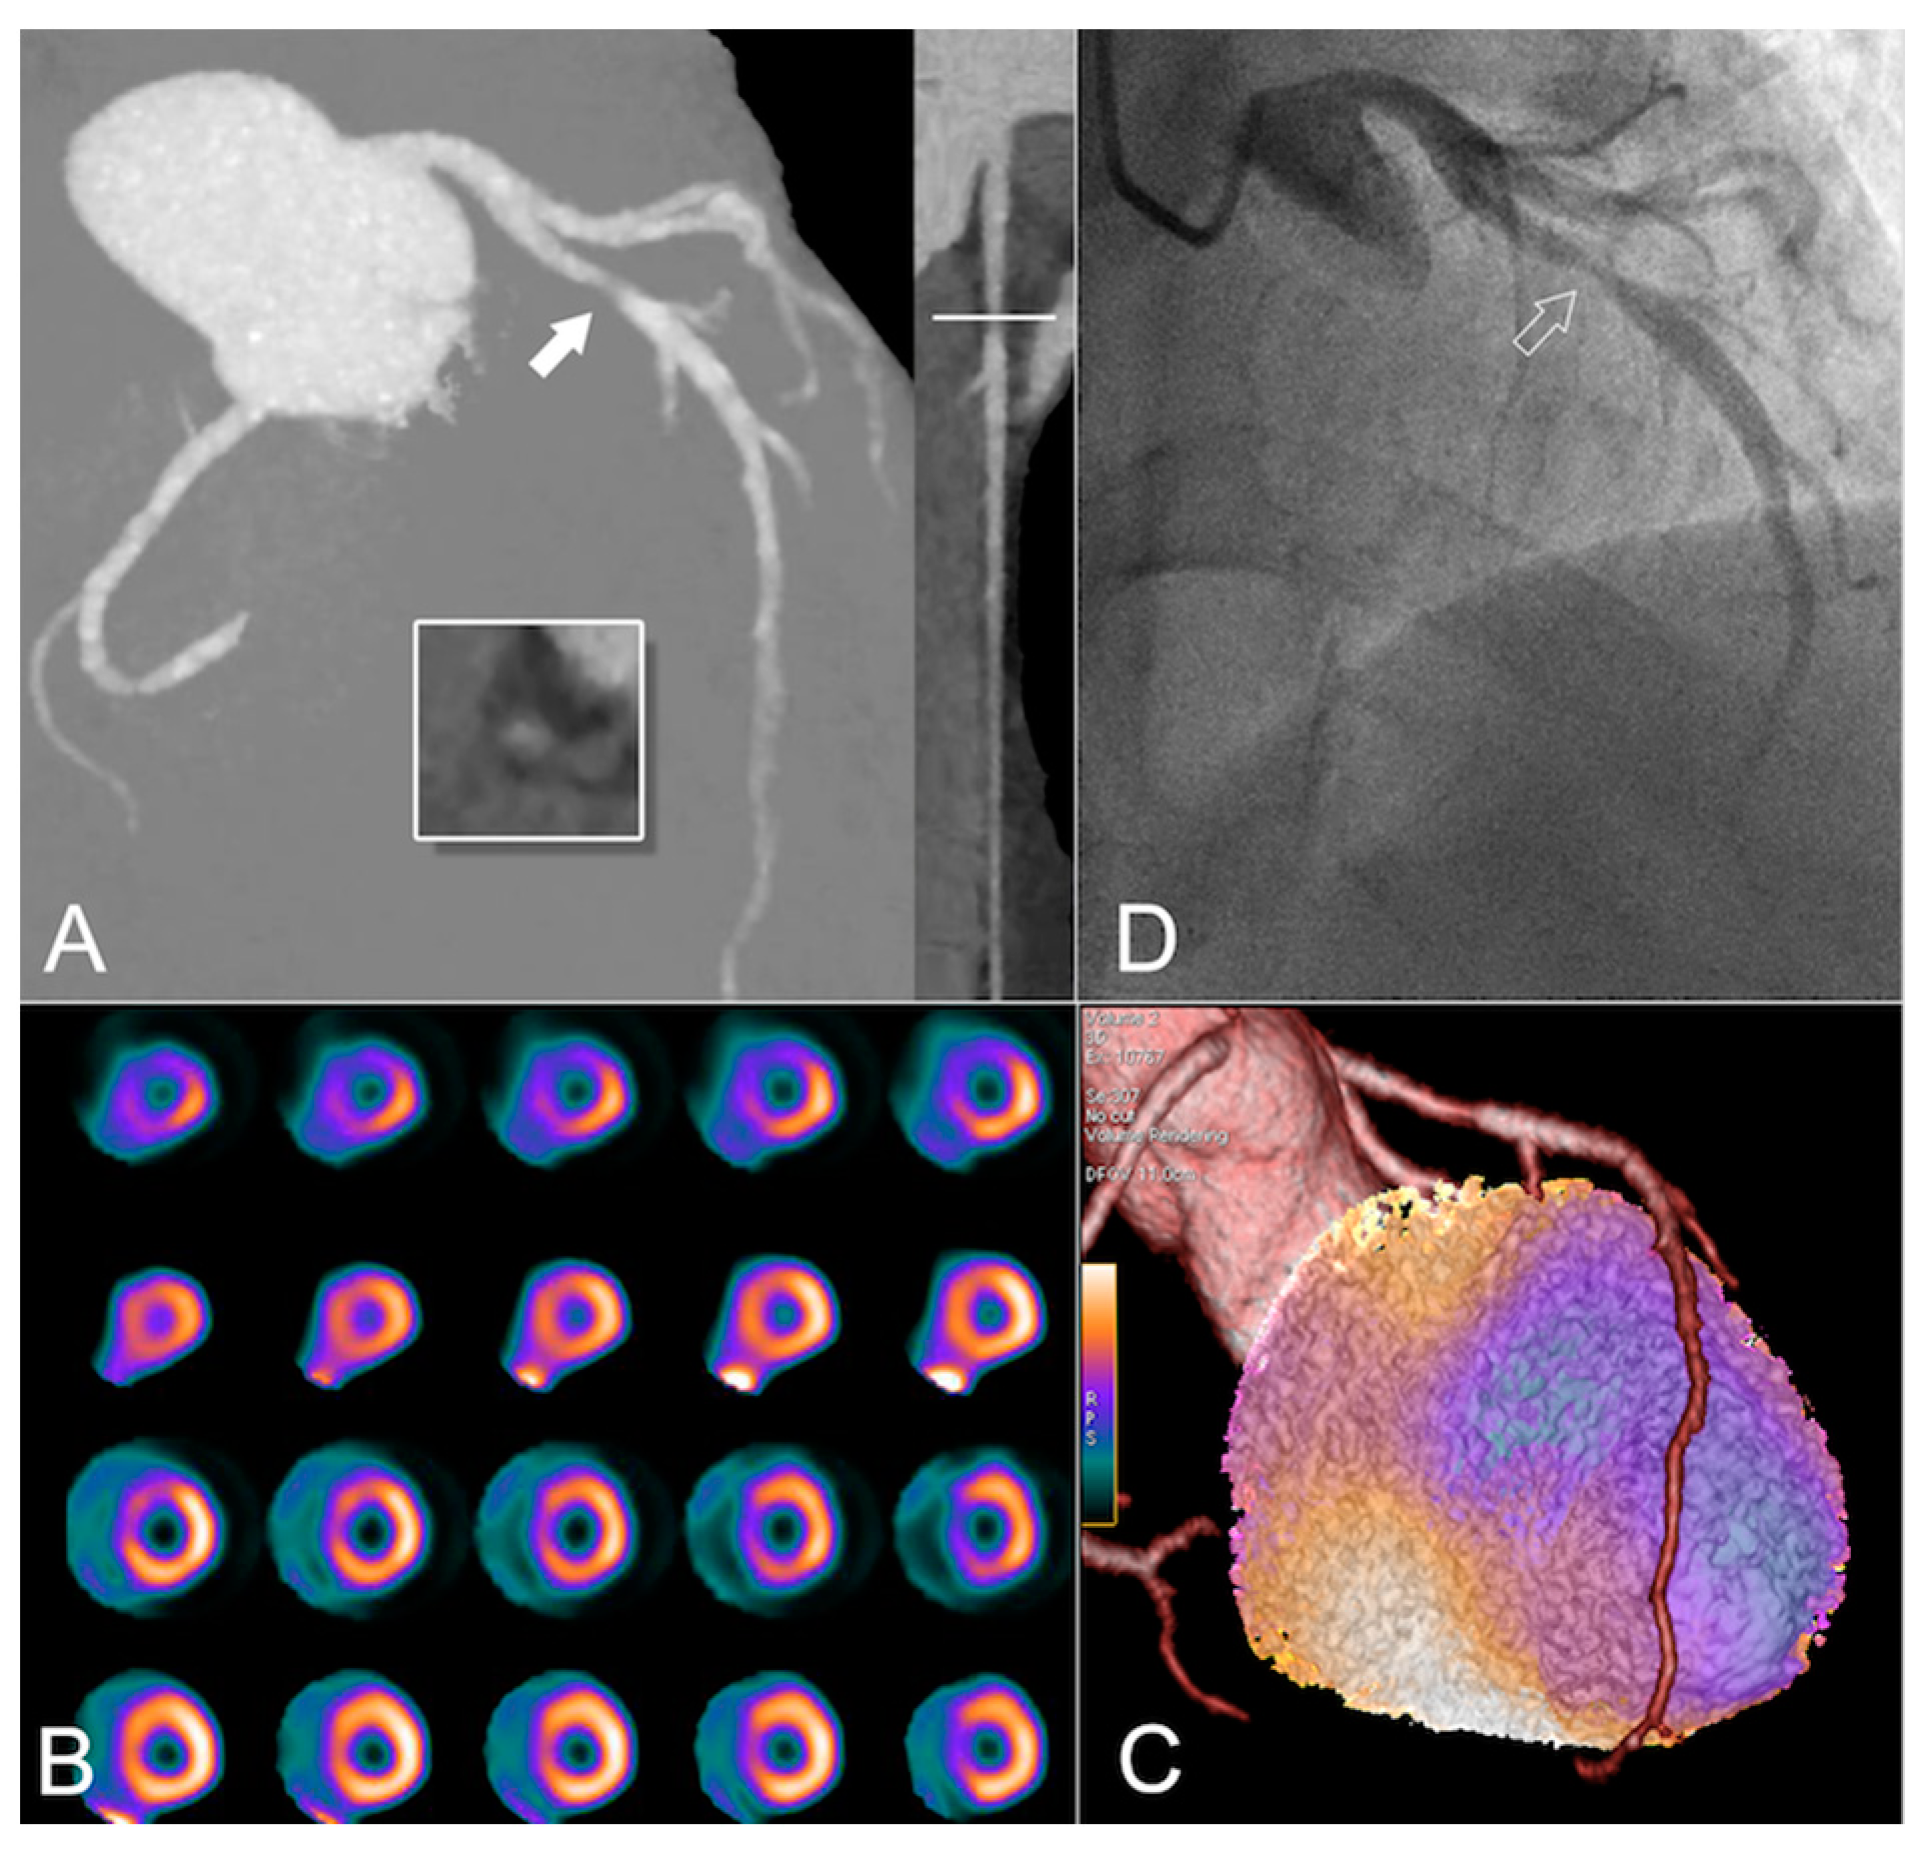

3. Coronary Artery Calcium (CAC) Scoring

6. 18F-Fluorodeoxyglucose Positron Emission Tomography (FDG PET)